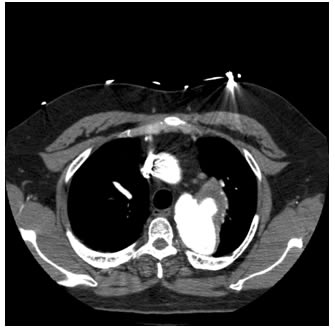

The patient is a 33 year old male with a history of juxtaductal coarctation who underwent a repair early in infancy. The patient had a recurrence of the coarctation and underwent a second open repair and left diaphragm plication at 2 years of age. He was lost to follow-up until recently when he presented to an emergency room with a several week history of hemoptysis and left back pain. The patient’s physical exam was remarkable only for a well-healed left thoracotomy incision. The patient was afebrile with equal blood pressures in all 4 extremities. The patient’s white count was normal. A CT scan of the chest demonstrated a saccular aneurysm of the proximal descending thoracic aorta measuring approximately 6cm in diameter (Figure 1). The patient was transferred to the Oregon Health and Sciences University for further management.

The patient had an uneventful postoperative course. He had no left arm symptoms. A postoperative CT scan showed good placement of the endoprosthesis and vascular plugs and no endoleak (Figure 6). The patient was discharged to home on postoperative day 2.